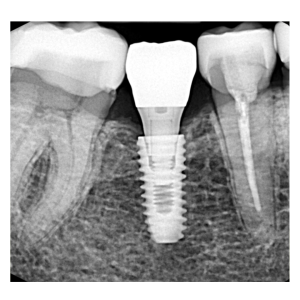

インプラント治療の症例

インプラント治療の症例です。

| 主訴 |

歯が抜けているのが目立つ |